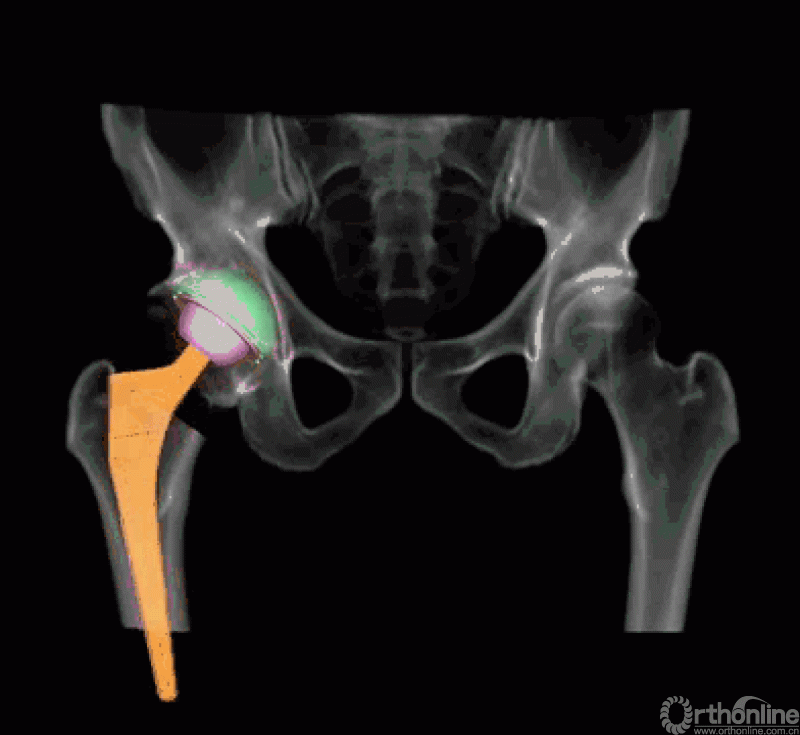

而后,由人工智能判断患者双侧腿长差及股骨偏心距大小,如图可见,由于长期受到的髋关节撞击征影响,该患者术前腿长差为2mm,右侧股骨偏心距为43mm,明显大于左侧股骨偏心距35mm。

AI HIP系统智能安放54mm直径的强生Pinnalce髋臼杯

最后,AI HIP系统根据患侧股骨颈干角、偏心距偏大的特殊情况,智能选择使用高偏高颈干角假体,对下肢等长和等偏心距重建做出了精准设计。根据系统预测结果,术中使用54mm Pinnalce髋臼杯、12号CORAIL高偏股骨柄、36mm 陶瓷股骨头、小转子上23mm截骨,实现髋关节的个体化、精准化重建。